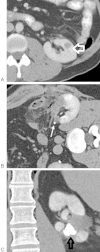

Although percutaneous ablation of small renal masses is generally safe, interventional radiologists should be aware of the various complications that may arise from the procedure. Renal hemorrhage is the most common significant complication. Additional less common but serious complications include injury to or stenosis of the ureter or ureteropelvic junction, infection/abscess, sensory or motor nerve injury, pneumothorax, needle tract seeding, and skin burn. Most complications may be treated conservatively or with minimal therapy. Several techniques are available to minimize the risk of these complications, and patients should be appropriately monitored for early detection of complications. In the event of a serious complication, prompt treatment should be provided. This article reviews the most common and most important complications associated with percutaneous ablation of small renal masses.